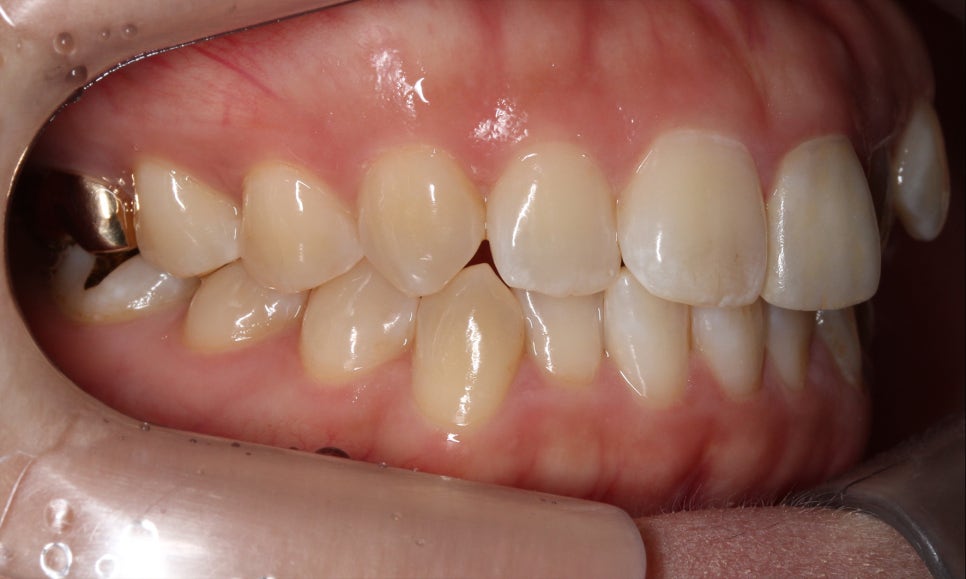

양악교정 전 치아의 교합평면 모습을 보면

송곳니교정을 하지 않아 견치의 높이가

상당히 올라가 있는 모습입니다.

덧니의 경우 영구치가 맹출되는

시기로 인해 송곳니에서 주로

발생하게 되는데요, 이러한 덧니는

종종 회전되거나 틀어진 치아와

혼동하기 쉽습니다.

이러한 치아들과 덧니를 구별하는

가장 쉬운 방법은 위처럼 치아가

맹출된 높이를 확인하는 것인데요,

위의 Case처럼 송곳니가 주변 치아들보다

더 위쪽으로 뻐드러지게 맹출되어 있는 것을

high canine라고 합니다.